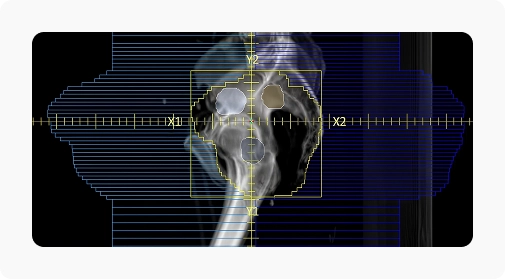

- IGRT: лучевая терапия с визуальным контролем;

Технологии визуализации и контроля: kV CBCT, MV EPID и BPS (авторская SGRT-система LinaTech).

ИИ совмещает kV CBCT, MV EPID и BPS изображения, чтобы повысить точность облучения.

| Система визуализации | kV-CBCT , MV-EPID |

| Максимальное поле обзора CBCT [см] | 35 |

| Разрешающая способность CBCT [пара линий/см] | ≥12 |

| Разрешение матрицы детектора | 2816х2816 |